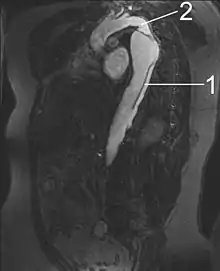

By separating a portion of the wall of the artery (a layer of the tunica media or in some cases tunica intima), a tear creates two lumens or passages within the vessel, the original or true lumen, and the false lumen created by the new space within the wall of the artery. It is not yet clear if the tear in the innermost layer, the tunica intima, is secondary to the tear in the tunica media. Dissections originating in the tunica media are caused by disruption of the vasa vasorum. It is thought that dysfunction in the vasa vasorum is an underlying cause of dissections.[2]

Arterial dissections become life-threatening when growth of the false lumen prevents perfusion of the true lumen and the related end organs. For example, in an aortic dissection, if the left subclavian artery orifice were distal to the origin of the dissection, then the left subclavian would be said to be perfused by the false lumen, while the left common carotid (and its end organ, the left hemisphere of the brain) if proximal to the dissection, would be perfused by the true lumen proximal to the dissection.

Vessels and organs that are perfused from a false lumen may be well-perfused to varying degrees, from normal perfusion to no perfusion. In some cases, little to no end-organ damage or failure may be seen. Similarly, vessels and organs perfused from the true lumen but distal to the dissection may be perfused to varying degrees. In the above example, if the aortic dissection extended from proximal to the left subclavian artery takeoff to the mid descending aorta, the common iliac arteries would be perfused from the true lumen distal to the dissection but would be at risk for malperfusion due to occlusion of the true lumen of the aorta by the false lumen.